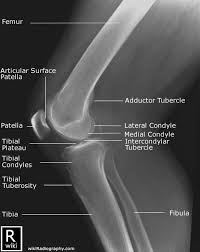

The patella or kneecap is seen sitting in front and to the left of the femur. A lateral view x ray shows the knee from the side. The image here is a front to back view of the knee joint also called the ap view.